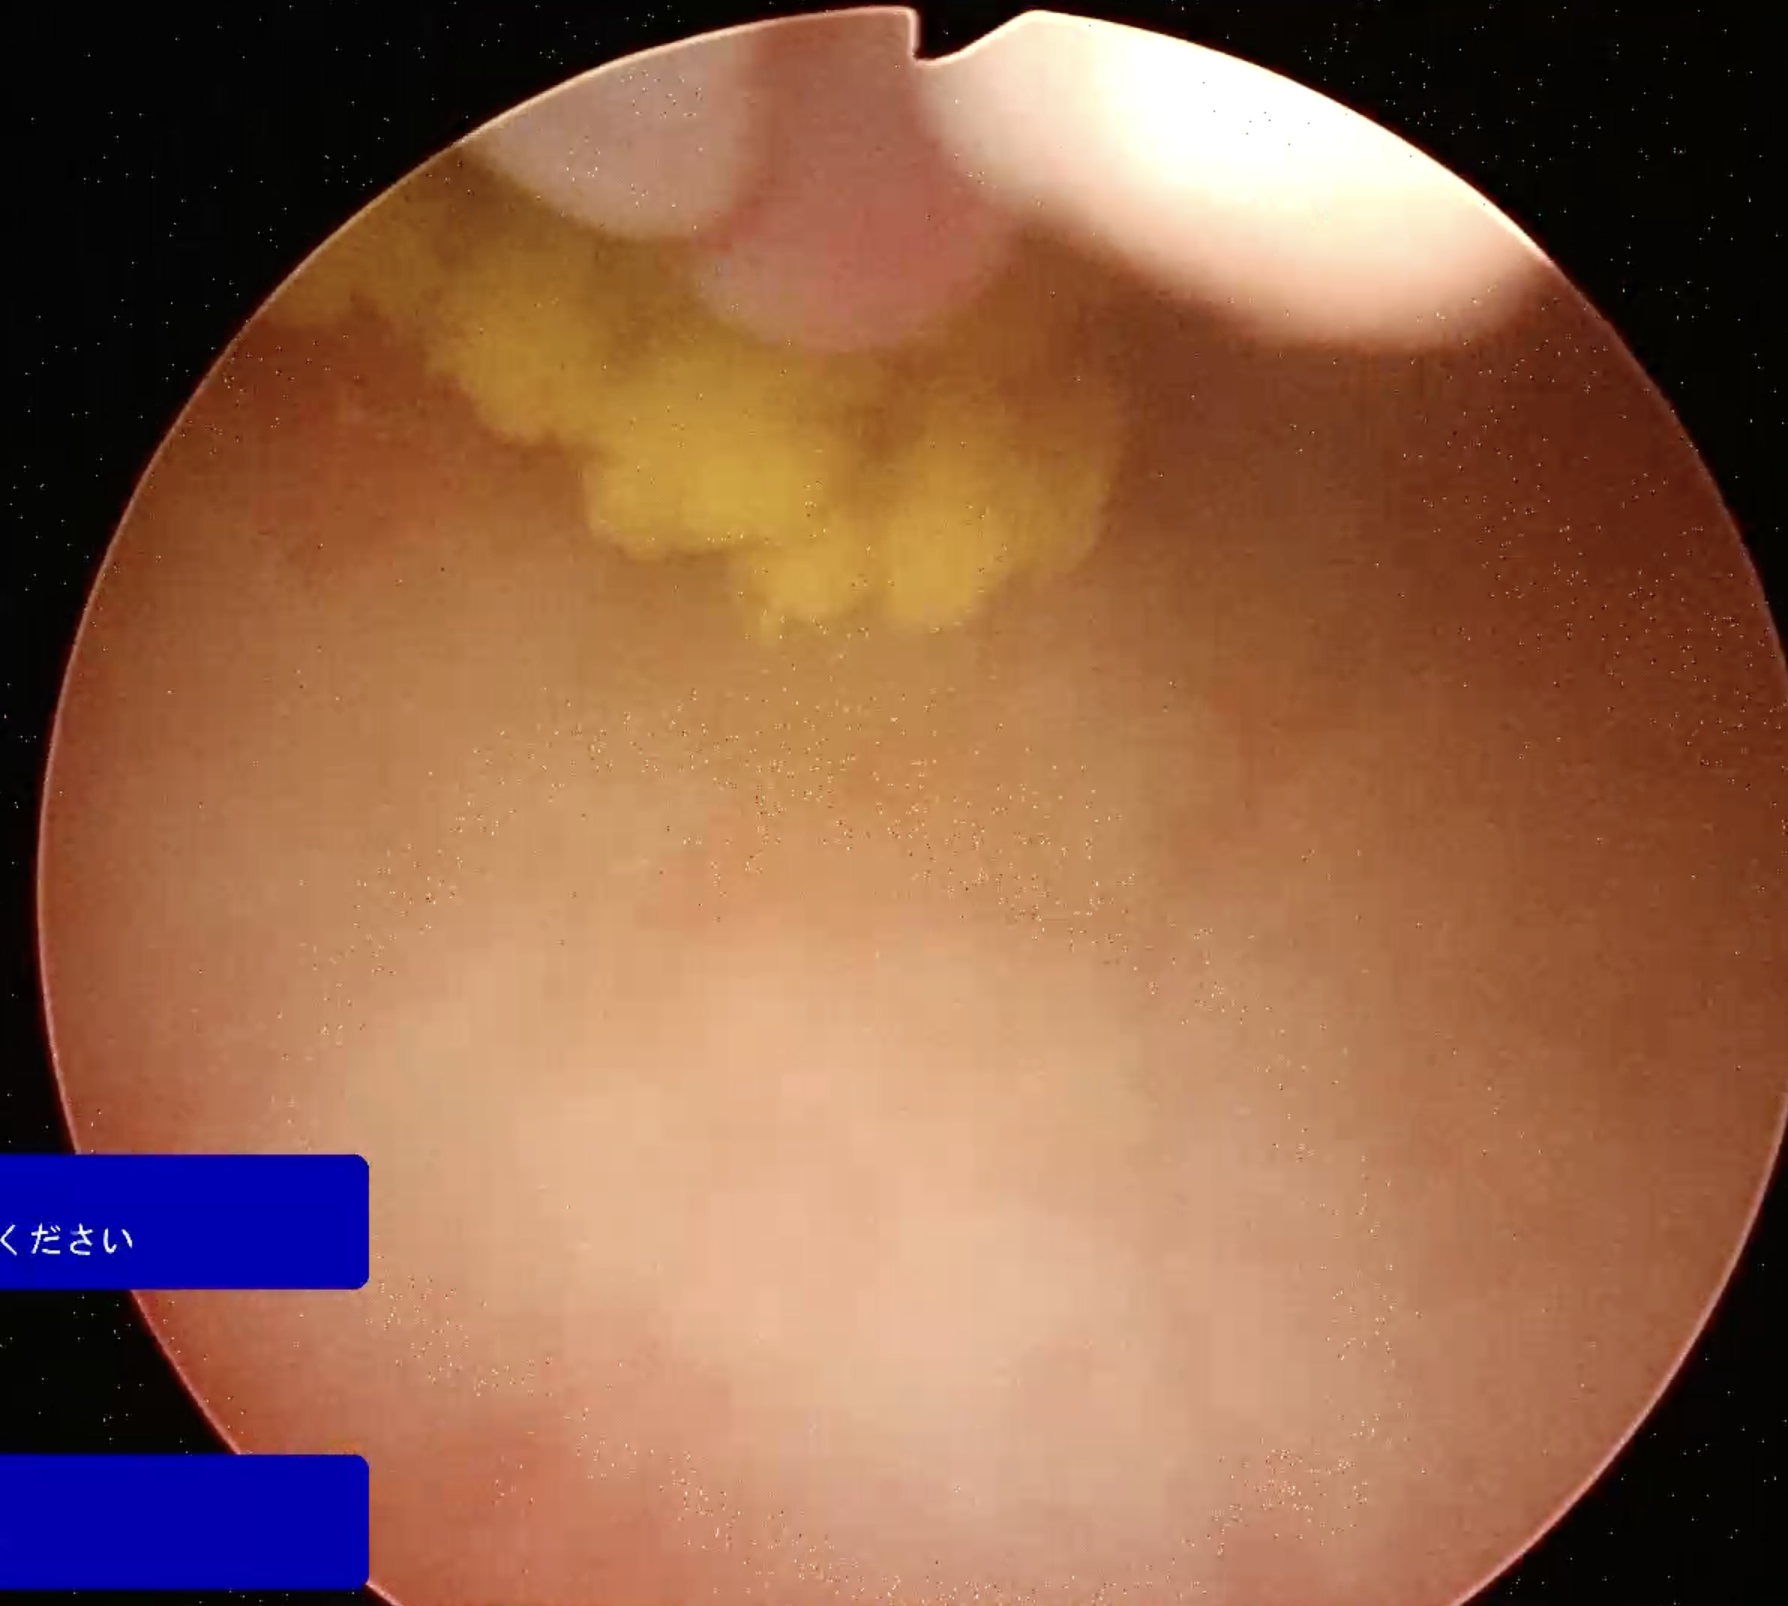

当院では、腹腔鏡を使用することで手術の際にお腹を切らずに一部穴を開けるだけで、結石を取ることが可能です。

しかも腹腔鏡のスコープでは膀胱の内部をくまなく見ることができるため、かなり細かい結石であっても目視して取り出せるため、石の取り残しのリスクが大幅に減少します。

以下に写真を載せてあります。